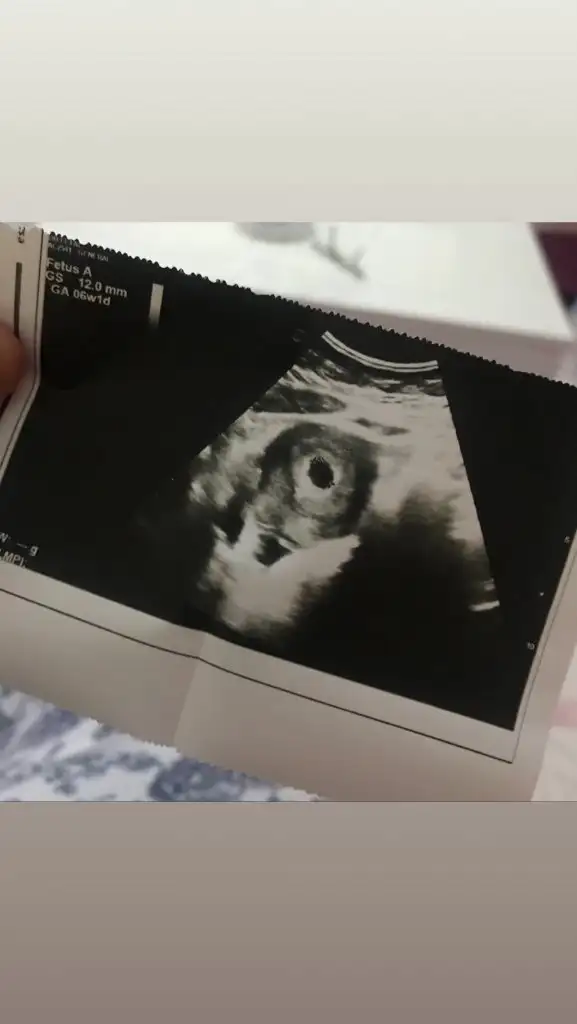

Son adetim 14 eylül .. bugün tam 6yız yarın 6+1 le devam edicez Allahın izniyle..kızlar sizlerde ultrason resmlernizi yüklermisinizKac haftalık dedi doktor canım. Son adet hangi gundu senin

5 gun var aramızda.Son adetim 14 eylül .. bugün tam 6yız yarın 6+1 le devam edicez Allahın izniyle..kızlar sizlerde ultrason resmlernizi yüklermisiniz

Ozeldemi bakındın benimki cok belli değil hastane den kaynaklı diyorum ama inşallah oyledirEki Görüntüle 2548527 benimde bu şekilde kızlar. sat 13 eylul. dun çekildi bu ultrason 6+1de![]()

Aa seninle sat tarihimiz aynı canımEki Görüntüle 2548527 benimde bu şekilde kızlar. sat 13 eylul. dun çekildi bu ultrason 6+1de![]()

burdakiler de benimki kadar net değil nedense. devlet hastanesi canımOzeldemi bakındın benimki cok belli değil hastane den kaynaklı diyorum ama inşallah oyledir![]()

Evet canem benm bidaki kontrolüm 9unda tam 8 ken gidicz inşallah kalbni duyarız..görüntü olarak gördk güp güp oynuyodu yavrum kıyamam..sesini duyamadk henüz5 gun var aramızda.